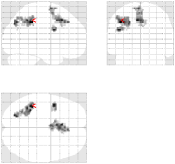

Concerning the Lc-Rc contrast on the data acquired with , Fig. 7 [top] shows that all reconstruction methods enable to retrieve the expected activation in the right precentral gyrus. However, when looking more carefully at the statistical results (see Tab. 2), our pipeline and especially the 4D-UWR-SENSE algorithm retrieves an additional cluster in the right middle frontal gyrus. On data acquired with , the same Lc-Rc contrast elicits similar activations, i.e. in the same region. As demonstrated in Fig. 7 [bottom], this activity is enhanced when pMRI reconstruction is performed with our pipeline. Quantitative results in Tab. 2 confirm numerically what can be observed in Fig. 7: larger clusters with higher local -scores are detected using the 4D-UWR-SENSE algorithm, both for and . Also, a larger number of clusters is retrieved for using wavelet-based regularization.

In order to investigate the smoothing effect introduced by our algorithm, spatial smoothing in the pre-processing pipeline has been turned off and statistical results are illustrated in Fig. 7 [right] and Tab. 2 (Unsmoothed 4D-UWR-SENSE). As expected, qualitative and quantitative results show that deactivating the spatial smoothing gives slightly higher -score values for activation maxima. However, smaller activated clusters are detected compared to results obtained based on smoothed data. As regards the temporal regularization effect, statistical results (not shown here) obtained with 3D-UWR-SENSE reconstructed images show intermediate performance which lies between those of the 2D (UWR-SENSE) and 4D (4D-UWR-SENSE) versions. Indeed, such a regularization helps improving the BOLD signal contrast which allows us to retrieve higher activation peaks.

| mSENSE | UWR-SENSE | 4D-UWR-SENSE | Unsmoothed 4D-UWR-SENSE | |

|---|---|---|---|---|

|

|

|

|

|

|

|

|

|

| cluster-level | voxel-level | |||||

| p-value | Size | p-value | T-score | Position | ||

| mSENSE | 79 | 6.49 | 38 -26 66 | |||

| UWR-SENSE | 144 | 0.004 | 5.82 | 40 -22 63 | ||

| 21 | 0.064 | 4.19 | 24 -8 63 | |||

| 4D-UWR-SENSE | 189 | 0.001 | 7.03 | 34 -24 69 | ||

| 53 | 0.001 | 4.98 | 50 -18 42 | |||

| 47 | 0.001 | 5.14 | 32 -6 66 | |||

| Unsmoothed 4D-UWR-SENSE | 112 | 0.001 | 7.26 | 34 -24 69 | ||

| 21 | 0.001 | 4.77 | 32 -6 66 | |||

| 19 | 0.001 | 4.98 | 50 -18 42 | |||

| mSENSE | 0.006 | 21 | 0.295 | 4.82 | 34 -28 63 | |

| UWR-SENSE | 33 | 0.120 | 5.06 | 40 -24 66 | ||

| 4D-UWR-SENSE | 51 | 0.006 | 5.57 | 40 -24 66 | ||

| Unsmoothed 4D-UWR-SENSE | 25 | 0.001 | 5.7 | 40 -24 66 | ||

Fig. 8 reports on the robustness of the proposed pMRI pipeline to the between-subject variability for this motor contrast. Since sensory functions are expected to generate larger BOLD effects (higher SNR) and appear more stable, our comparison takes place at . Two subject-level Student’s -maps reconstructed using the different pMRI algorithms are compared in Fig. 8. For the second subject, one can observe that the mSENSE algorithm fails to detect any activation cluster in the right motor cortex. By contrast, our 4D-UWR-SENSE method retrieves more coherent activity for this second subject in the expected region.